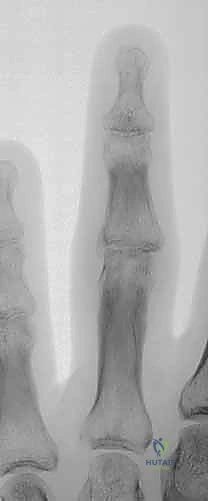

Figure 1A demonstrates a typical, more severe dorsal fracture-dislocation, involving approximately 65% of the volar articular surface.

Figures 1B and 1C illustrate proximal interphalangeal joint volar dislocations.

Pilon fractures, specifically, show marked comminution of the middle phalanx base.

Figures 1D and 1E depict proximal interphalangeal joint pilon fractures.

Figure 2A shows the distal end of the proximal phalanx, a convex surface composed of two condyles, articulating with the concave surface of the proximal end of the middle phalanx.

Research and clinical experience have shown that the PIP joint will generally remain stable if up to 42% of the volar half of the middle phalanx articular surface is damaged, as assessed on a true lateral radiograph.

Figure 3B visually represents this concept of volar loss and its implications for instability.

However, fellows, be aware that in practice, subluxation can occur with as little as 10% to 15% joint surface loss, though this is less common. More severe injuries, involving a greater portion of the volar lip, are longitudinally unstable, leading to persistent PIP joint subluxation and the clinical findings we'll discuss. For pilon fractures, the proximal phalanx condyles are driven into the middle phalanx base, displacing the central articular surface distally and splaying the dorsal-volar and lateral margins. This injury pattern is inherently longitudinally unstable, resulting in proximal migration, diminution or obliteration of the joint space, and significant articular incongruity.